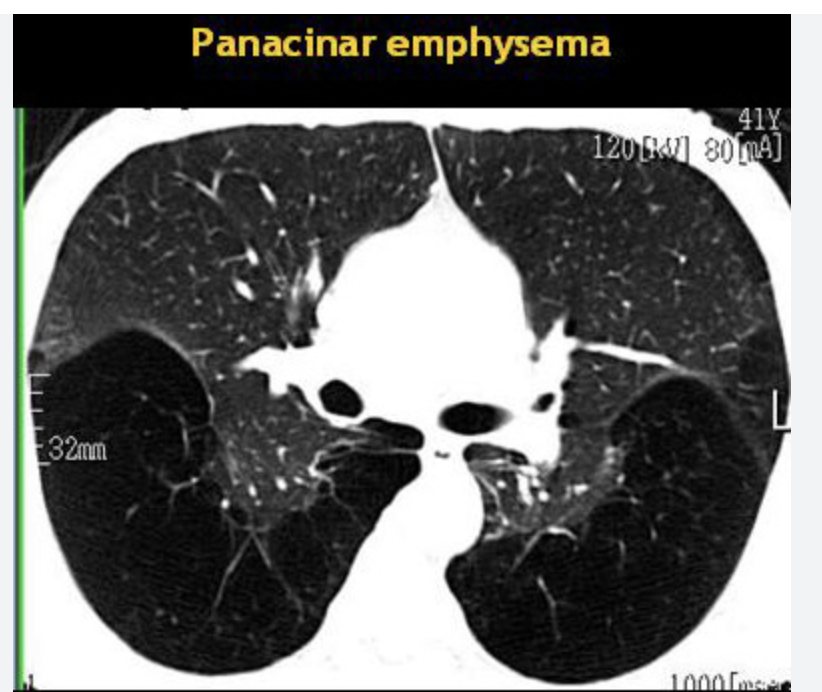

El déficit de α1-antitripsina es la única alteración genética conocida que predispone al desarrollo de EPOC. Provoca enfisema precoz (por debajo de 45 años) en fumadores y es del tipo panacinar.

EPoc entre 20 y 50 con enfisema y casi siempre con antecedentes o sea deficiencia alfa 1 antitripsina

Que tipo de enfisema se asocia a deficiencia de alfa 1 antitripsina